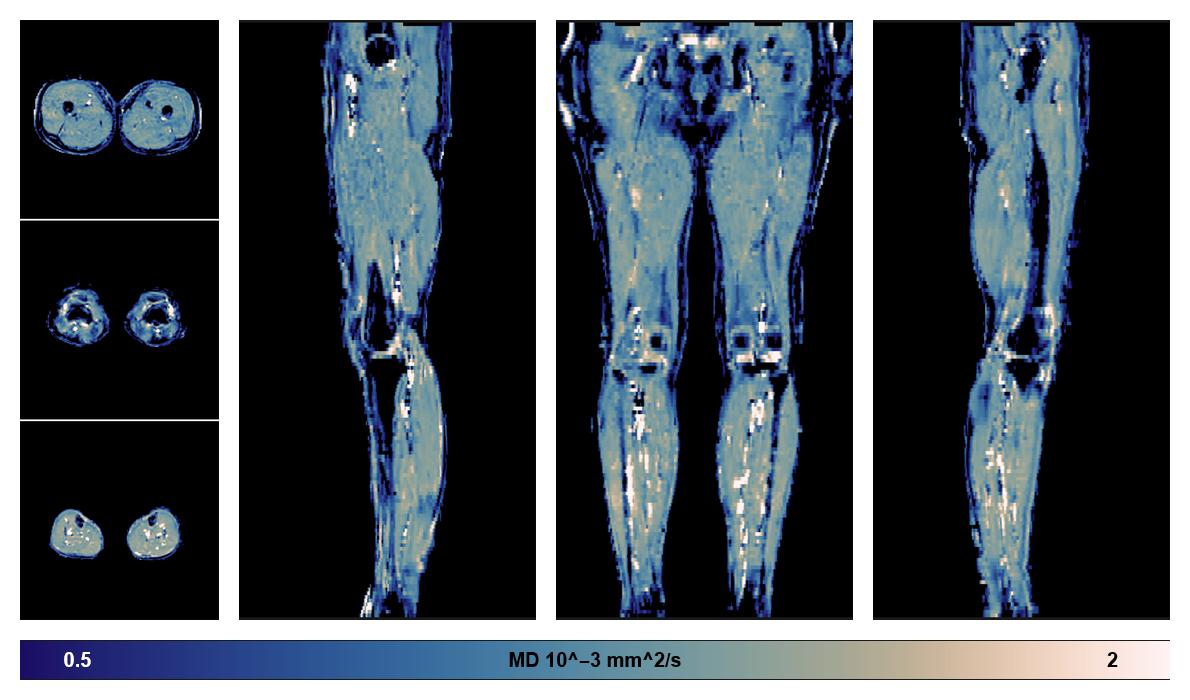

• Mean diffusivity

IVIM corrected whole leg muscle mean diffusivity obtained from diffusion tensor imaging.